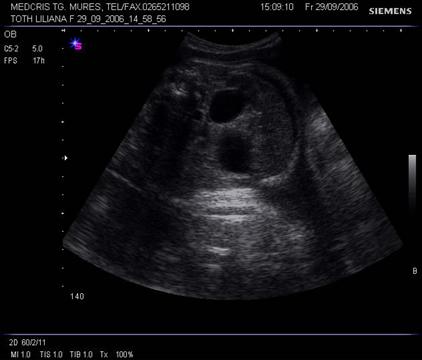

Fig. nr.277. Dilatatie bilaterala bazinetala renala la 28 sapt, sectiune transversala lombara, fat cu sindrom de valva uretrala posterioara

Fig. nr.278. Sindrom de valva uretrala posterioara, la fatul de 28 sapt. sex masculin, se remarca dilatatia bilaterala bazinetala moderata, vezica urinara destinsa,